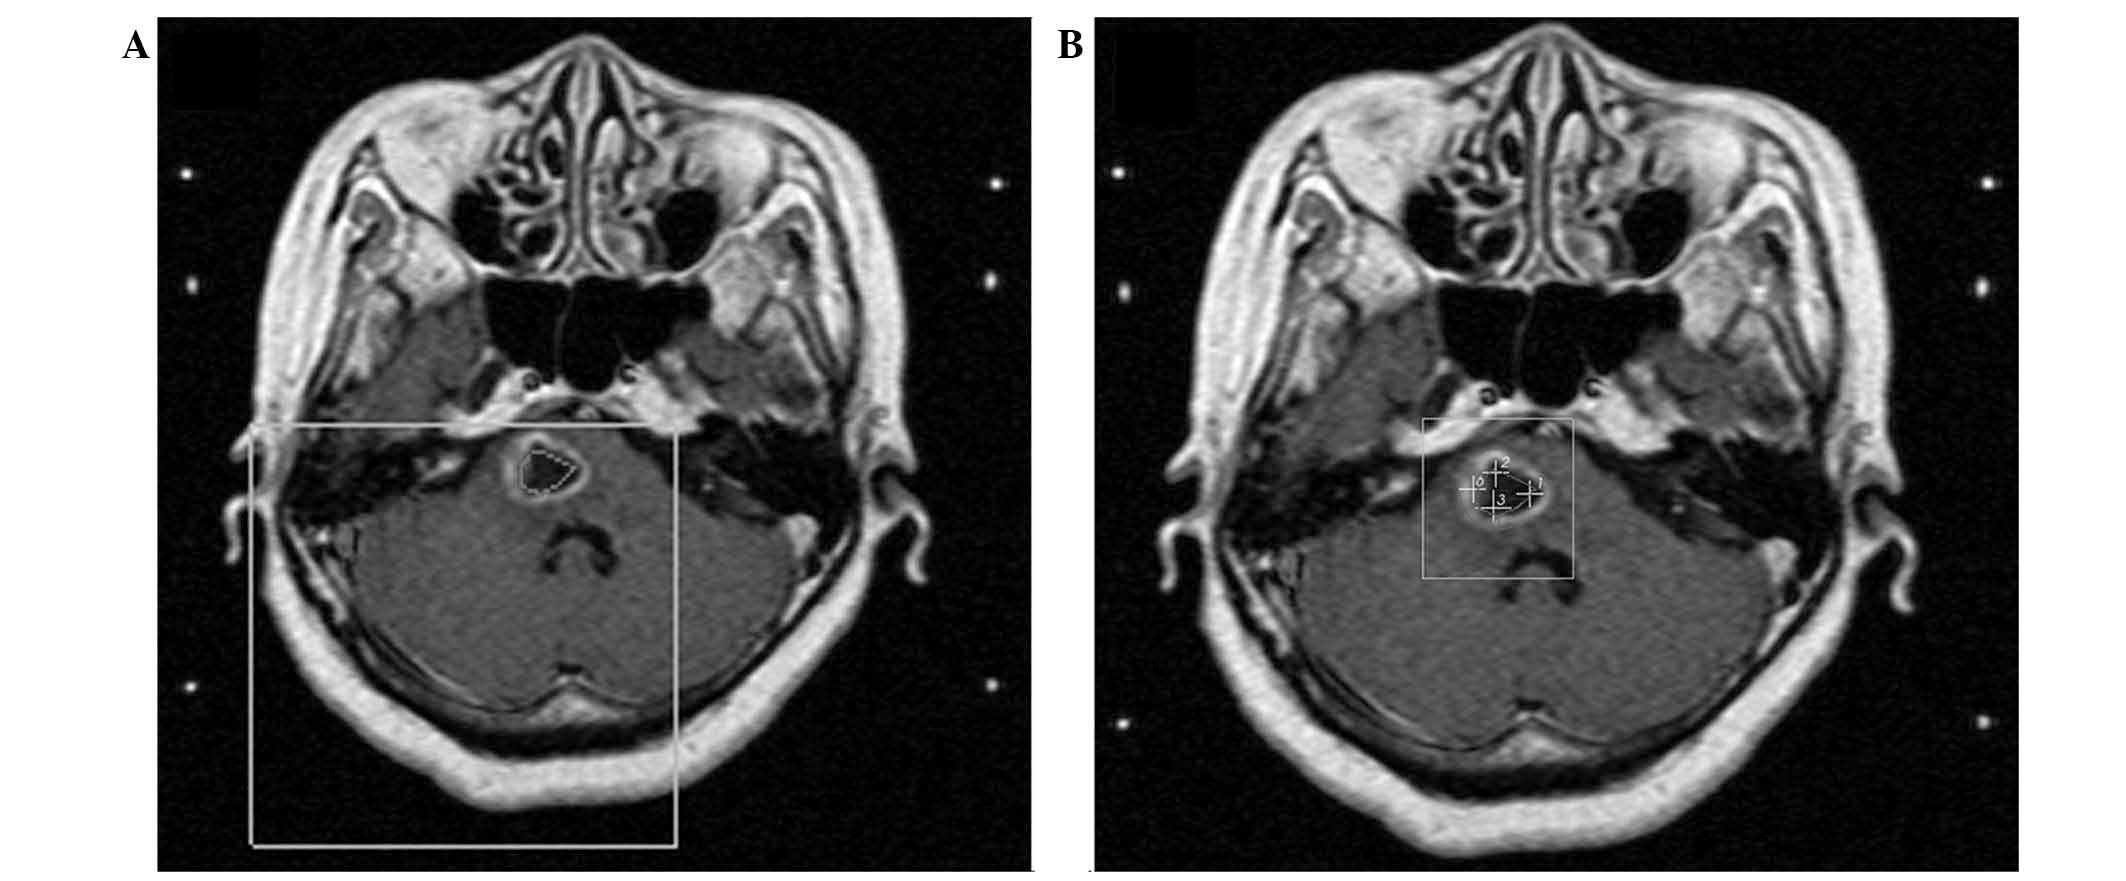

Brainstem metastases have a poor prognosis and are difficult to manage. The present study describes the first case of histopathologically‑confirmed brainstem metastasis originating from lung adenosquamous carcinoma, and discusses the outcomes of treatment by stereotactic aspiration combined with gamma knife radiosurgery (GKRS). A 59‑year‑old female presented with a cystic mass (15x12x13 mm; volume, 1.3 cm3) located in the pons, two years following surgical treatment for adenosquamous carcinoma of the lung. The patient received initial GKRS for the lesion in the pons with a total dose of 54.0 Gy, however, the volume of the mass subsequently increased to 3.9 cm3 over a period of three months. Computed tomography‑guided stereotactic biopsy and aspiration of the intratumoral cyst were performed, yielding 2.0 cm3 of yellow‑white fluid. Histology confirmed the diagnosis of adenosquamous carcinoma. Aspiration provided immediate symptomatic relief, and was followed one week later by repeat GKRS with a dose of 12.0 Gy. The patient survived for 12 months following the repeat GKRS; however, later succumbed to the disease after lapsing into a two‑week coma. The findings of this case suggest that stereotactic aspiration of cysts may improve the effects of GKRS for the treatment of cystic brainstem metastasis; the decrease in tumor volume allowed a higher radiation dose to be administered with a lower risk of radiation‑induced side effects. Therefore, stereotactic aspiration combined with GKRS may be an effective treatment for brainstem metastasis originating from adenosquamous carcinoma.

Figure 1